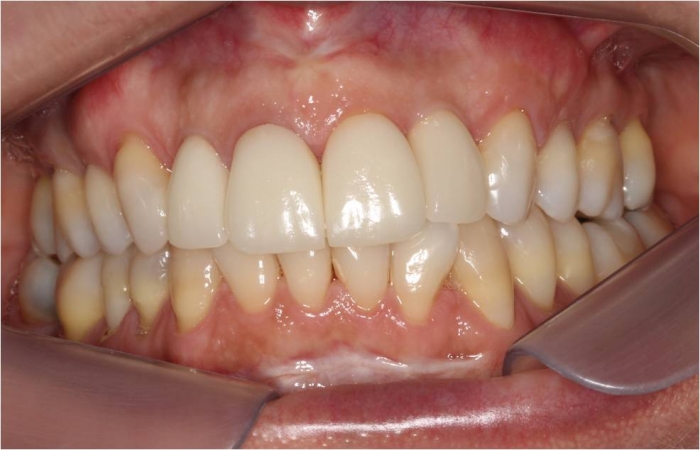

Imagem final da prótese em porcelana instalada sobre o implante - Clínica Cliniface

Imagem final da prótese em porcelana instalada sobre o implante

Sorriso final, do caso terminado em Agosto de 2014 - Clínica Cliniface

Sorriso final, do caso terminado em Agosto de 2014